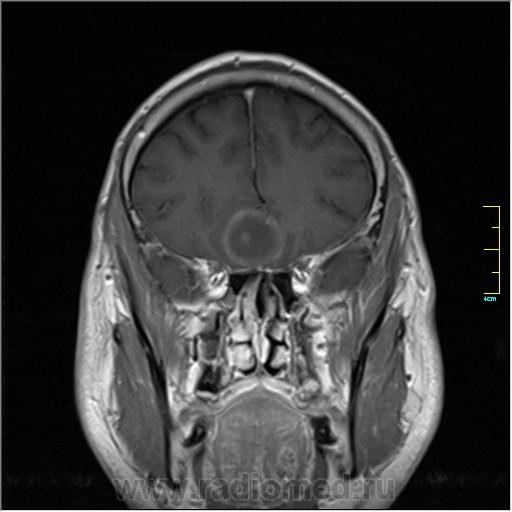

Пациентка направлена на исследование с диагнозом "Гипертонический криз"

Пациентка направлена на исследование с диагнозом "Гипертонический криз", энцефалопатия неуточненная.

частично функционирующая аневризма

Иначе говоря, аневризма с хронической геморрагией, т.к. мы видим фракции крови различного возраста.

По-моему, аневризма с пристеночными тромбами.

Постепенное пристеночное образование тромбов приводит к появлению типичного для аневризмы феномена -слоистости МР сигнала в полости аневризмы. Данная картина демонстрирует слоистый характер тромботических масс в полости аневризмы .Функционрирующая часть имеет низкий сигнал во всех режимах сканирования. Дополнительно-перифокальный отек.

А может более корректно интерпретировать как частично тромбированная аневризма... Уж коь речь идет о фракциях, ну то есть о тромбе по сути.... Ну и плюс перфокальный отек головного мозга (вероятнее цитотоксический+вазогенный).